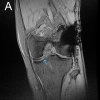

A 38-year-old female housewife presented to the outpatient department at RML Hospital with the chief complaint of pain in the left hip region that had persisted for 1 month. The patient had been asymptomatic until the sudden onset of pain, which began abruptly and progressively worsened over the initial 2 days. The pain was described as dull and aching in nature and was localized, not radiating to other regions. The discomfort was notably exacerbated by movements such as getting up from a sitting position, walking, and standing. However, the pain was alleviated by rest, the intake of painkillers, and lying down with the legs straightened. The patient reported no associated symptoms such as fatigue, weight loss, or loss of appetite. There was no history of trauma, fever, heavy exertion, or lifting weights that could have precipitated the condition. In addition, the patient denied having any chronic illnesses or a history of regular medication intake. Her past medical history was insignificant, with no previous significant illnesses or surgeries. The patient maintained a mixed diet and had a history of normal vaginal delivery. She reported a normal menstrual cycle with no irregularities. The family history was unremarkable for any similar musculoskeletal complaints or chronic diseases. Furthermore, the patient was a non-smoker and non-alcoholic, maintaining regular bladder and bowel habits. During the physical examination, tenderness was noted over the left anterior inferior iliac spine. No distal neurovascular deficits were observed, indicating that the nerve supply and blood flow to the area were intact. The range of motion in the left hip was assessed, revealing restricted and painful flexion up to 70°. Other movements of the hip, such as adduction, abduction, and extension, were painful but not restricted, suggesting that the primary issue was localized rather than affecting the entire hip joint. Plain radiograph of pelvis with bilateral hips revealed suspicious calcific deposits in the lip of the left acetabulum (Fig. 1). Patient was given analgesics and rest for some time but she had some relief. Later a high-resolution axial series was obtained computed tomography (CT) scan. The CT findings revealed calcification at the insertion of the left rectus femoris muscle, anterior to the anterior inferior iliac spine (Fig. 2). Both hip joints appeared normal with no evidence of articular surface erosion, indicating that the joints themselves were not the source of the pain. The acetabular cups were normal in morphology, suggesting that the hip sockets were intact and unaffected. No significant joint effusion was seen, ruling out any major inflammatory process within the hip joint. The bilateral sacroiliac joint spaces were normal, indicating that the pain was not originating from these joints. In addition, the rest of the visualized muscles and soft-tissue planes were unremarkable, further localizing the problem to the insertion of the rectus femoris muscle. Correlating the CT findings with a magnetic resonance imaging (MRI) study, the diagnosis of calcific tendonitis at the insertion of the left rectus femoris muscle was confirmed. The MRI findings supported the absence of any significant abnormalities in the hip joints and surrounding structures, corroborating the diagnosis made through CT imaging (Fig. 3). Based on the clinical presentation, physical examination, and imaging studies, the patient was diagnosed with calcific tendonitis at the insertion of the left rectus femoris muscle, anterior to the anterior inferior iliac spine. The patient was advised to continue rest and avoid activities that exacerbated the pain, with follow-up visits scheduled to monitor progress and response to treatment.